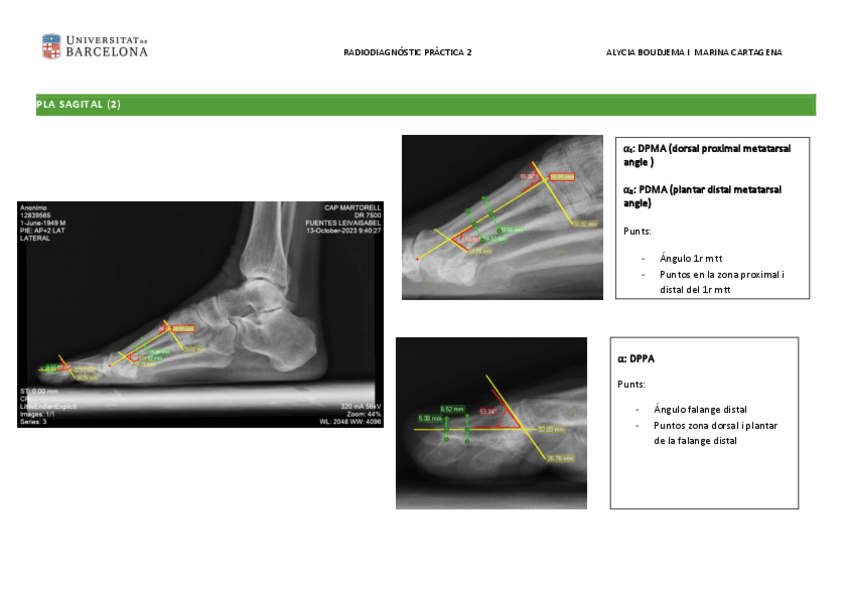

He publicado nuevos apuntes de 3º Radiodiagnóstico y Radioprotección Podológica: radiodiagnostic-practiques-alison-i-marina.pdf